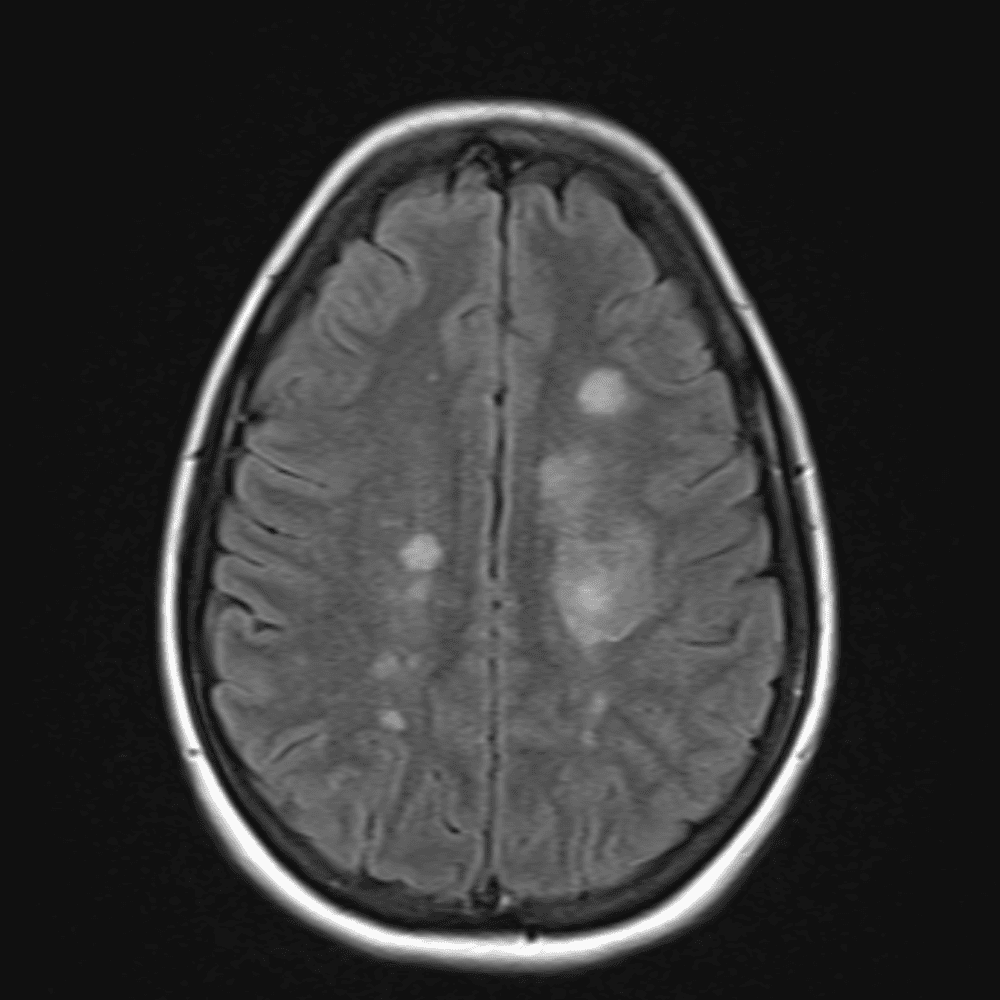

๋‹น์ง ์‹œ ํ”ํžˆ ๋ณผ ์ˆ˜ ์žˆ๋Š” ์‚ฌ๋ก€์˜ ์ „ํ˜•์ ์ธ ์˜ˆ๋ฅผ ํฌํ•จํ•ฉ๋‹ˆ๋‹ค.

39 ์‚ฌ๋ก€

์—ฐ์Šต

๋ฏธ๋ฌ˜ํ•˜๊ฑฐ๋‚˜ ์–ด๋ ค์šด ์‚ฌ๋ก€์™€ ์ผ๋ถ€ ์ •์ƒ ์‚ฌ๋ก€๋ฅผ ํฌํ•จํ•˜์—ฌ ๋‹น์ง์„ ์‹œ๋ฎฌ๋ ˆ์ด์…˜ํ•ฉ๋‹ˆ๋‹ค.

50 ์‚ฌ๋ก€